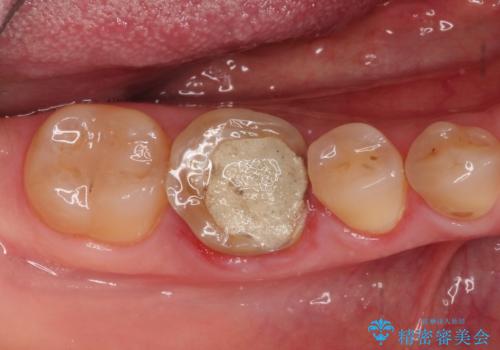

[ 深い虫歯・根管治療・セラミッククラウン ]複合した問題を持った虫歯治療

![[ 深い虫歯・根管治療・セラミッククラウン ]複合した問題を持った虫歯治療の症例 治療前](https://seimitsushinbi.jp/wp/wp-content/uploads/2022/09/b464b4c5c3053a5fc84212fb664a039f-500x350.jpg?v=1663667230)